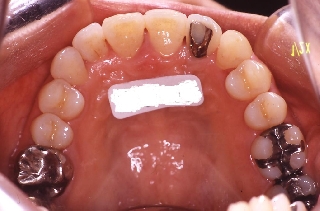

治療前 治療後

上顎 上顎 上顎